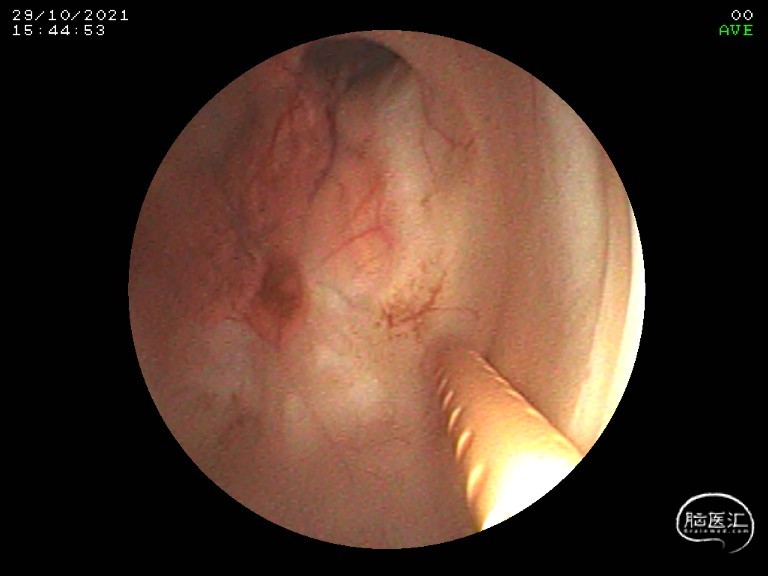

入院第三天2021-10-29经左额原手术骨孔进行电子软性内镜下脑室探查,发现导水管仍被陈旧性凝血块堵塞,第四脑室流出道闭塞,形成孤立第四脑室,清除导水管内凝血块后在内镜下直接将引流管置入第四脑室。